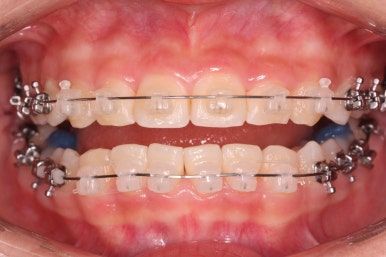

치료 종료 후의 모습입니다.

치아들이 가지런하게 되었고, 나오지 못하던 치아도 잘 나와서 가지런해졌습니다.

해당 부위 앞뒤로 쓰러져 있던 치아들도 축이 바로 잡혔고, 자연스레 위-아래 치아의 중앙선도 맞아졌습니다.

부산치아교정잘하는곳 키다리아저씨치과에서 이번 청소년 환자분께 치료하느라 소요된 기간은 총 16개월이였습니다.

얼굴 모습의 큰 변화 없이 양호한 모습 그대로 마무리가 되었고, 웃을 대 위아래 치아의 중앙이 안맞았던 부분도 개선되었습니다.